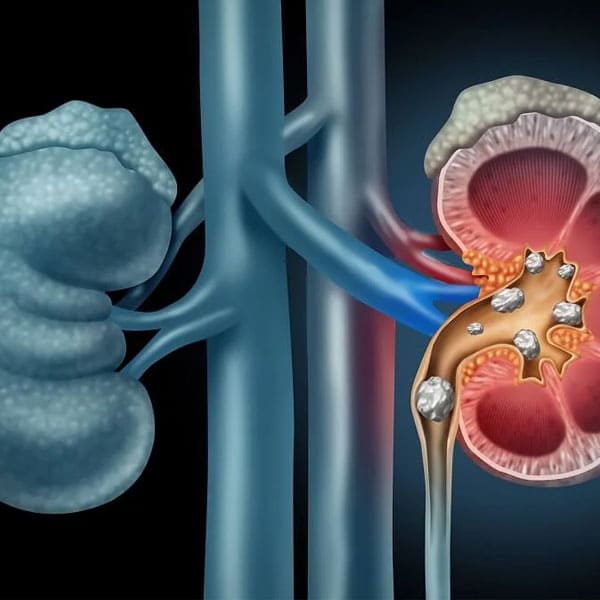

Diagnóstico, tratamiento y prevención de litiasis renal

La formación de piedras en los riñones tiende a ser recurrente, es necesaria una evaluación nefrológica para prevenir y tratar este padecimiento.